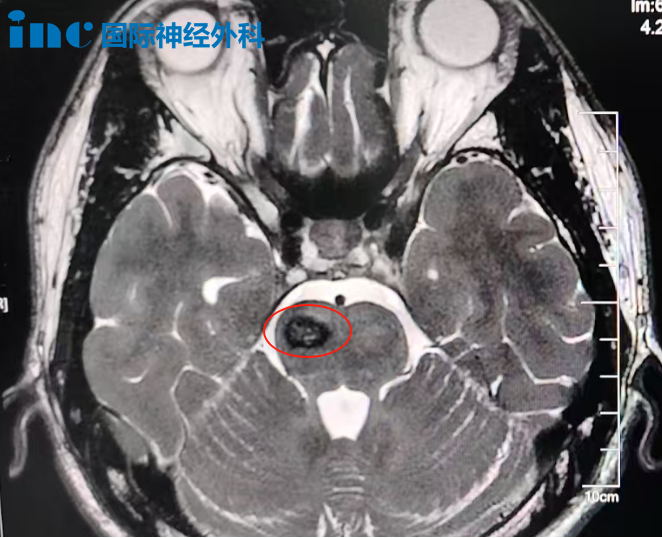

吴先生的病灶位于大脑脚中脑腹侧面,毗邻脚间窝。这处位置深藏于大脑核心,手术入路通道极为狭窄,周围密集排布着负责控制对侧肢体运动的神经纤维。一旦操作失当,轻则引发偏瘫,重则全身瘫痪。动眼神经同样穿行于此——手术中的任何闪失,都可能造成瞳孔散大、复视或眼睑下垂,而且这些损伤很可能是终身性的。

巴教授仔细审阅了术后核磁共振影像后说道:"这是一份非常漂亮的复查结果。桥脑内仅有极少量局部瘢痕形成,含铁血黄素沉积量也比其他患者术后的影像低得多。实际上,不能更好了。"